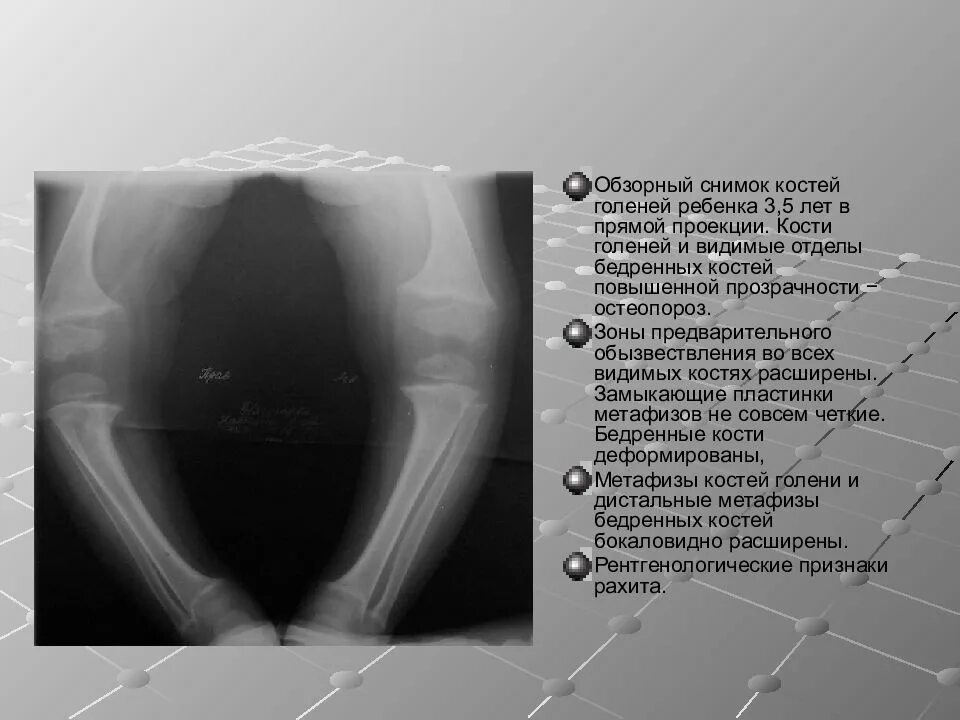

Снимок в прямой проекции